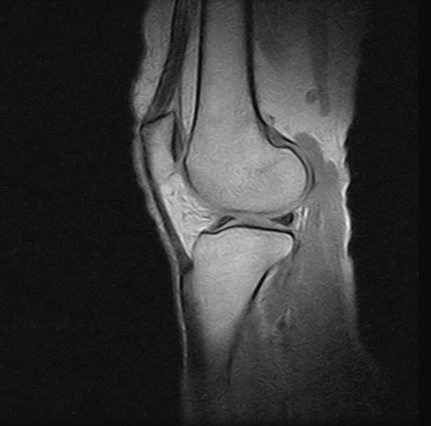

Ressonâncias Magnéticas Joelho

Se você pesquisa ressonâncias magnéticas joelho com eficiência e profissionalismo, não deixe de vir conhecer os serviços oferecidos pela RM Brasil.